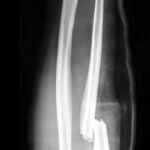

Arm Fractures are a common injury that occurs with falls, especially in aging individuals or those whose bones may not be as strong. Some of the most common fractures include the hand (scaphoid), wrist (radius), and upper arm (proximal humerus). The important thing is these fractures are not something that has to keep you from doing the activities you love.